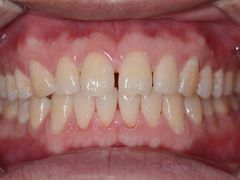

• 新达口腔(华东理工大学店)

• -新达口腔(华东理工大学店)